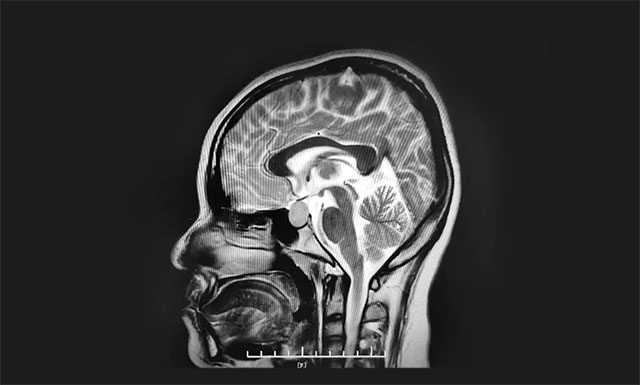

▲ 垂体大腺瘤超蝶鞍生长

鞍区MRI平扫+增强显示:蝶鞍稍扩大,鞍底骨质下陷;鞍内垂体偏左见一枚类椭圆异常信号,大小约1.6*1.4*1.4cm,垂体柄缩短,视交叉上抬。

神经外科6B病区主任潘仁龙主任指出,患者垂体瘤较大,属于垂体大腺瘤,患者的头痛和生理期异常就是垂体瘤在作祟。并且肿瘤已经压迫视神经,手术指征明确,无明显手术禁忌,应及时手术,否则往后发展患者视力也会受损。